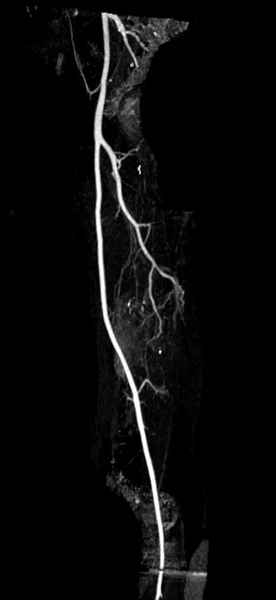

В зависимости от характера опухоли некоторые патологические переломы имеют риск кровотечения во время операции. Множественные литературные данные подтверждают, что надо проявить осторожность при интрамедуллярном остеосинтезе при неизвестных опухолях, особенно где имеется подозрение на Renal Cell Carcinoma. (RCC- hypernephroma) http://www.bonetumor.org/tumors/pages/page64.html

Со слов, больная ничем не болела, только последние 3 месяцев чувствовала боли в бедренной области. КТ брюшной полости подтвердил увеличенную правую почку. (5-6)

Для предупреждения кровотечения во время рассверливания, за день до операции провели эмболизацию сосудов питающий метастаз. http://radiology.rsnajnls.org/cgi/reprint/150/3/673.pdf (7-11, 12-15-16)